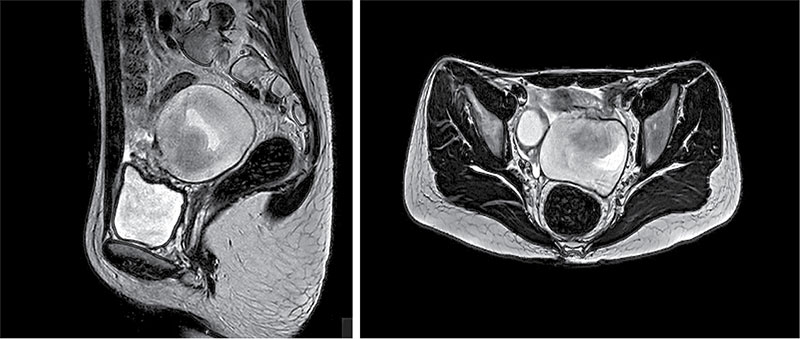

Рис. 3. Пациентка А., 11 лет: интраоперационная картина старого перекрута левых придатков матки

Пациентке выполнили операцию лапароскопическим методом. Интраоперационно при ревизии органов брюшной полости и малого таза обнаружен старый перекрут левых придатков матки на 360° вокруг собственной оси в диаметре до 8 см (рис. 3). Правые придатки матки без особенностей. Тело матки нормального размера с серозным блестящим покровом. В связи с нежизнеспособностью левых придатков матки принято решение о выполнении аднексэктомии слева. Некротизированное образование извлечено из брюшной полости в эндобаге. Макропрепарат: стенка конгломерата гладкая, синюшно-черного цвета, содержимое представляет собой сгустки старой крови (рис. 4).